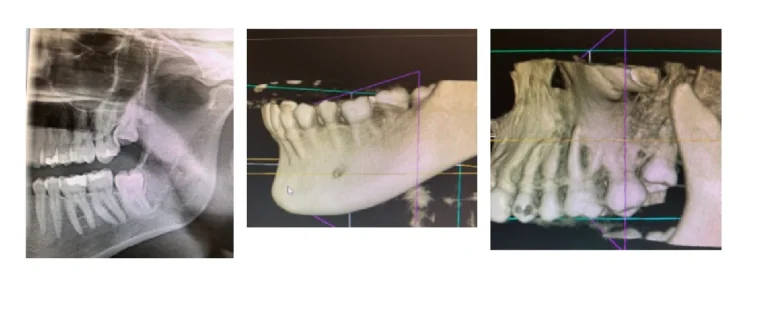

Here at The Briars, one part of my job is to take CB (cone beam) CT scans for both in-house and referred in patients. These scans produce 3D cross-sectional images of the jaw and of the teeth – it’s essentially a smaller, faster and safer version of a ‘normal’ CT scanner. The ‘cone beam’ element relates to the shape of the x-ray beam, which enables us to use a much lower radiation dosage, and shorter scanning time.

These scans can be required for a number of reasons, but many are sent over as part of the assessment for implant placement, or to investigate pathology associated with teeth that can’t always be seen on a 2D radiograph. These scans can show us bone structures, jaw structures, root canals, sinuses, even tumours. They can also be helpful with locating the origin of toothache – sometimes fractures in teeth aren’t always visible on a normal dental x-ray, but will show up on a 3D image. The CBCT scans are a fantastic, and fascinating diagnostic tool – and one of my favourite parts of the job!

The image on the left is a sectional 2D x-ray of the patient – the images in the middle and on the right make up part of their CBCT scan!

I took a scan for a patient last week, and we were both marvelling over the advances in technology – how wonderful it is that technology that was once restricted to a hospital setting can now be used in the dental practice. Not only is it more convenient to have all your treatment carried out under one roof – it also means you can avoid the evils of hospital parking! After I have scanned a patient, I show them the result on the screen, and check we have scanned all the areas that their dentist has requested. I often get asked the big questions by patients – ‘is the area suitable for an implant?’ ‘can you see if there is a fracture line?’ – but my qualification doesn’t go quite that far, and sadly I can’t answer their burning questions. What I can show them, is the 3D image of the area we’ve scanned – and for most, that is fascinating enough!